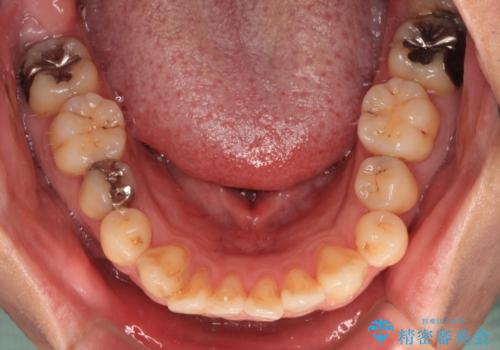

- 銀歯やむし歯でものが挟まるところが気になるとのことで来院された患者様です。

その他は銀歯のインレー(部分的な詰め物)が装着されており、それらはむし歯を除去した後にセラミックインレーにて修復治療を行い、左下と根管治療を行う左上の奥歯はオールセラミッククラウンにて補綴治療を行うこととしました。

根管治療の途中で、矯正治療の後戻りが気になるとのことで、下顎前歯の叢生を改善するためにマウスピース矯正を並行して行いました。